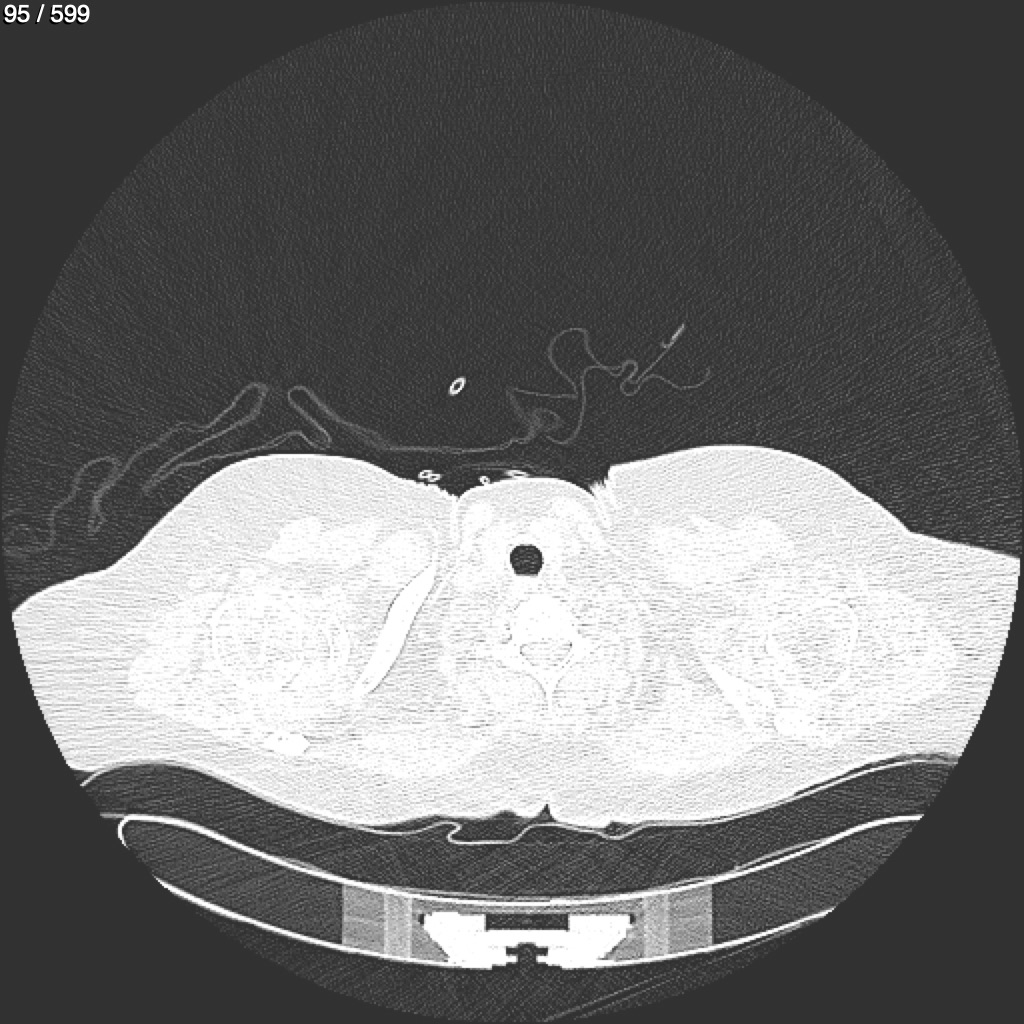

Home G​l​o​r​i​a​ ​G​l​a​d​y​s​ ​B​e​a​s​l​e​y​ ​-​ ​T​ó​r​a​x​ ​T​o​r​a​x​_​S​i​m​p​l​e​ ​(​A​d​u​l​t​o​)